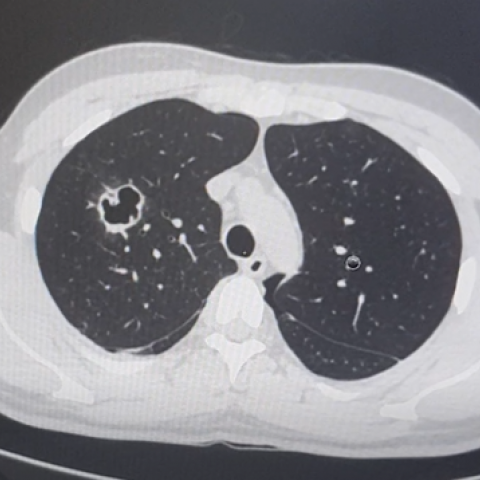

肺实变x线表现图片,肺不张x线表现图片

1 患者肺部影像学变化

胸部x线显示双侧气胸(左>右),右叶有薄壁空洞.

平片和ct:空洞是肺实变,肿块或者结节内的充气空隙,呈现透亮区或者低